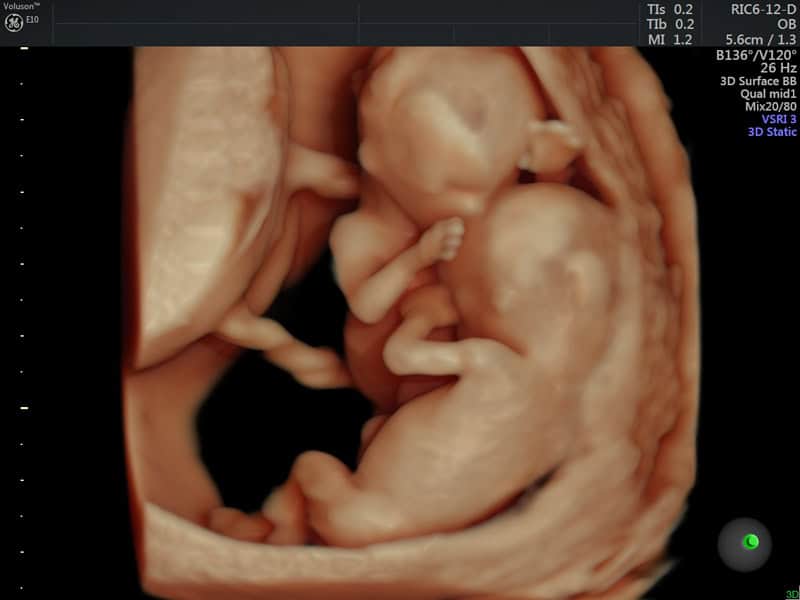

Επιπλέον, μέχρι τις 14 εβδομάδες κύησης, το έμβρυο κάνει στοχευμένες κινήσεις προς το τοίχωμα της μήτρας, καθώς και προς τα μάτια και το στόμα του. Αυτές οι σκόπιμες κινήσεις των εμβρύων ήδη από τις 14 εβδ. (12 εβδ. από τη σύλληψη), δείχνουν ότι το έμβρυο έχει συνείδηση και επίγνωση του περιβάλλοντός του. Εάν έχει δίδυμο αδελφάκι, θα απλώσει απαλά το χέρι του για να αγγίξει τον αδελφό του.

Ήδη από τις 14 εβδομάδες, τα δίδυμα αγγίζουν σκόπιμα το ένα το άλλο μέσα στη μήτρα. Το έμβρυο κινείται πιο απαλά όταν απλώνει το χέρι του προς στο πρόσωπο του δίδυμου αδελφού του.